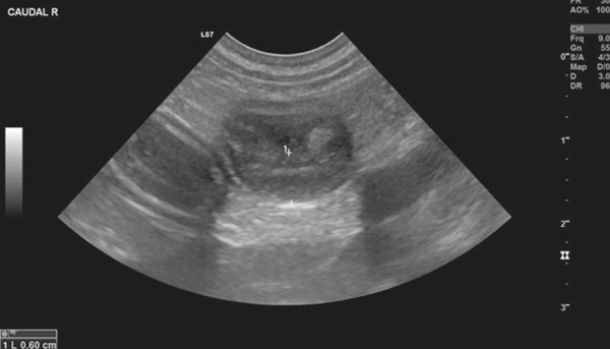

Diagnostic imaging forms a crucial part of clinical workup. Abdominal radiography might not be helpful as the changes in the gastrointestinal tract associated with AL depend on the disease severity, but we can observe a loss of detail or mass effect either due to the gastrointestinal mass and/or lymphadenomegaly or, less often, due to free abdominal fluid. Abdominal ultrasound is more commonly used. The most frequent ultrasonographic abnormality observed is abnormal wall layering with or without concurrent increase in wall thickness (Figure 1). The extent of wall changes can be highly variable in dogs with intestinal lymphoma. Where sonographic abnormalities were present, lesions have been characterised as: predominantly hypoechoic, focal or multifocal ulcerations, small hypoechoic nodules to larger masses (Figure 2) and enlarged abdominal lymph nodes (Figure 3). In some cases abdominal effusion may be present as well. The sonographic appearance of gastrointestinal lymphoma is variable and can overlap with that of a normal bowel, especially in cases of small cell or low-grade AL. Lastly, diffuse intestinal thickening has also been reported and it should be differentiated from enteritis. It is important to note that even when no ultrasonographical abnormalities are found, AL cannot be ruled out without obtaining biopsies of the gastrointestinal tract.